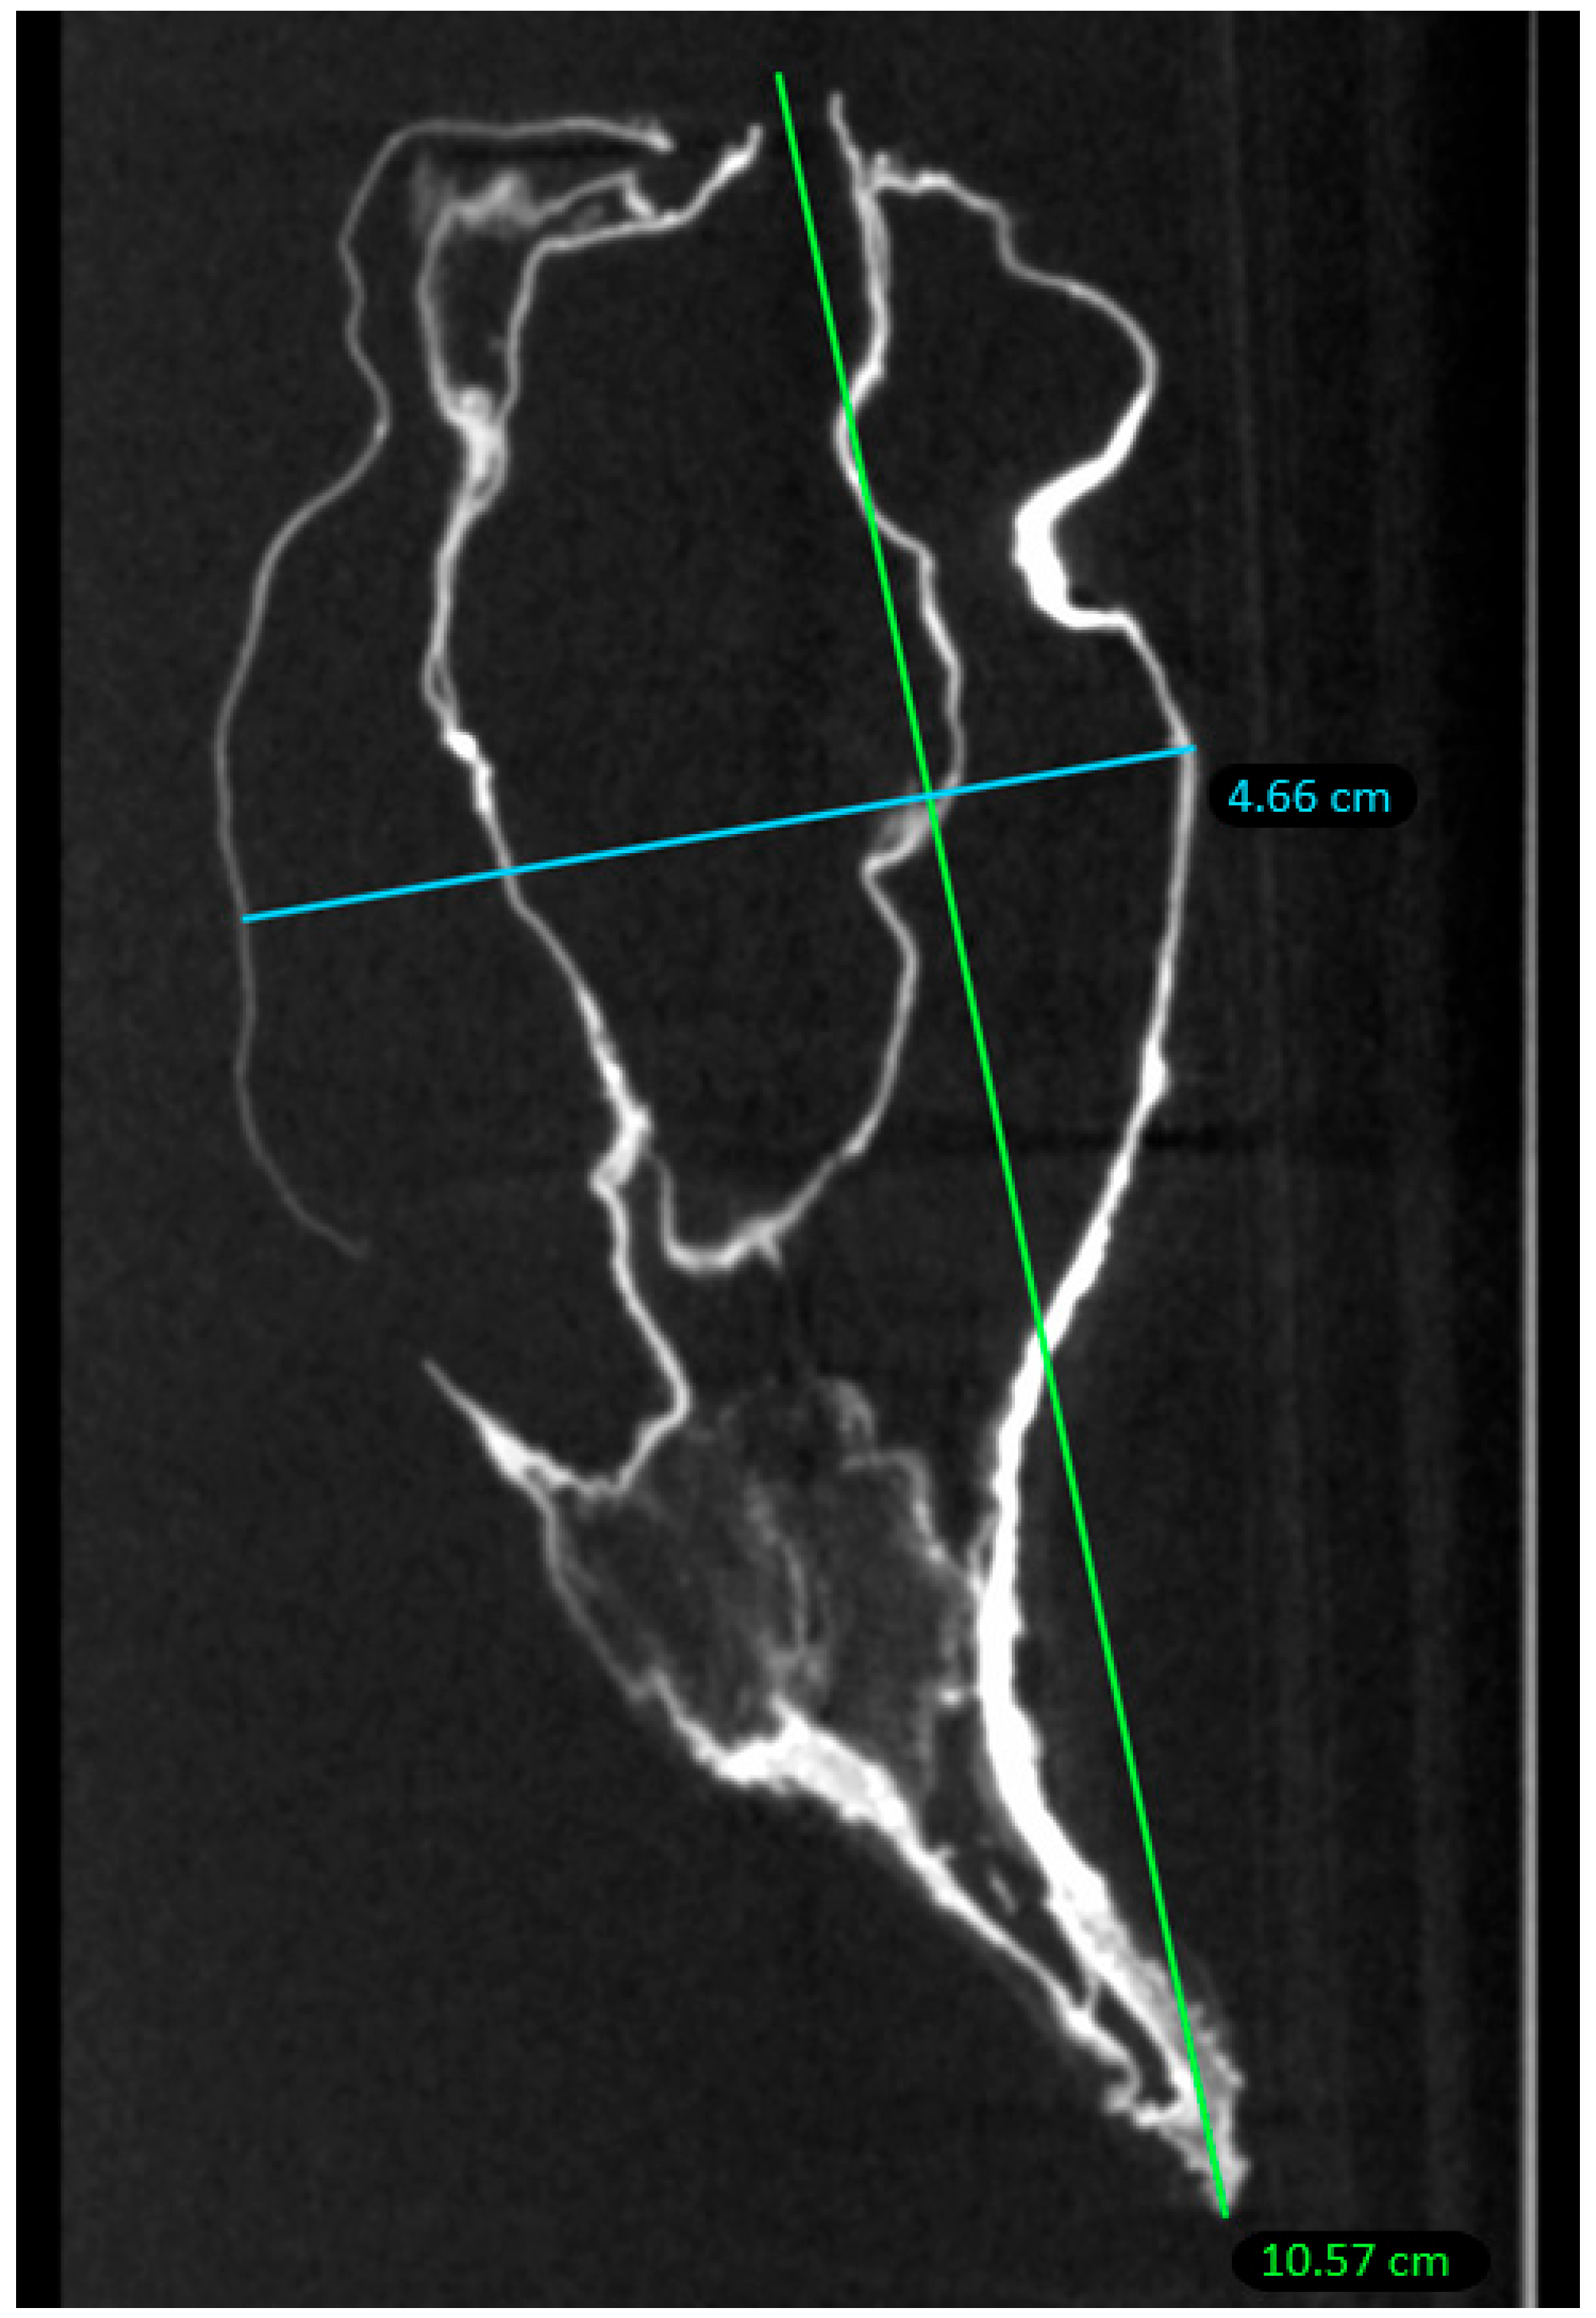

2.2. Micro-CT Scan

4.2. Micro-CT Scan